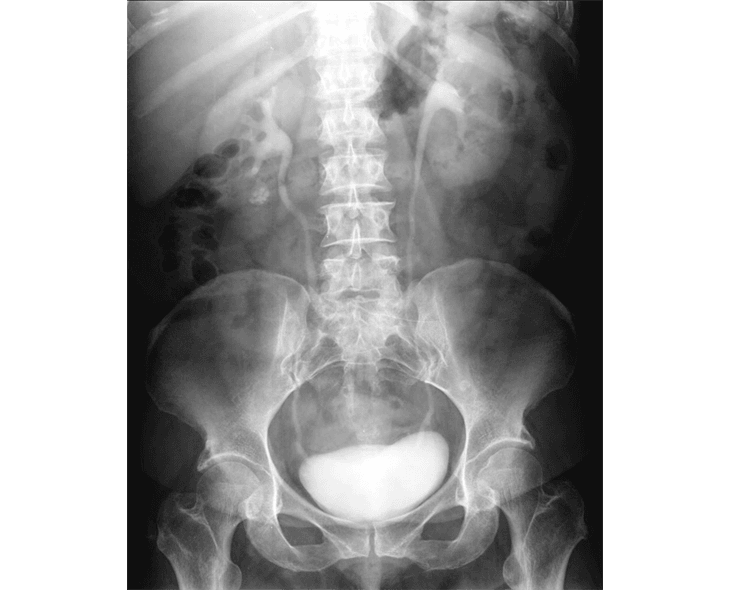

Aula 7 1 - Analise de Imagem por Raios x - I